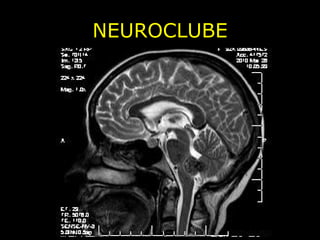

NEUROCLUBE